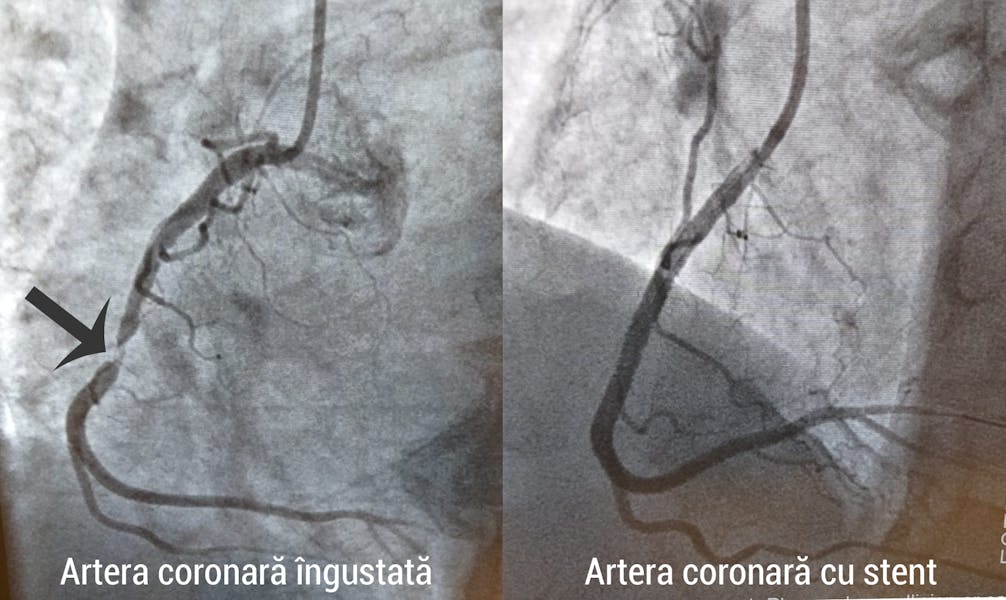

Angioplastia este o procedură minim-invazivă prin care vasele de sânge îngustate sunt lărgite cu ajutorul unui balon sau unui stent. Procedura se efectuează printr-o mică puncție, prin care medicul introduce tuburi subțiri de plastic (catetere) și le ghidează spre locul afectat. La acest nivel, introduce un balon mic, pe care îl umflă pentru a lărgi diametrul vasului, iar apoi îl îndepărtează. Dacă îngustarea vasului este mare, iar dilatarea cu balon nu este de ajuns, medicul va monta un stent pentru a menține artera deschisă.

Stentul este un dispozitiv metalic cilindric, care rămâne fixat pe peretele vasului de sânge și permite circulația normală a sângelui. Stenturile pot fi de mai multe feluri:

- La locul stenozei se introduce un balon care va fi umflat pentru a dilata vasul de sânge. Dacă acest proces nu este suficient, medicul va monta un stent. Montarea stentului este asemănătoare dilatării stenozei cu balon. În acest caz cateterul este prevăzut cu un balon cu stent. Astfel, în momentul umflării balonului, stentul va fi automat expandat.